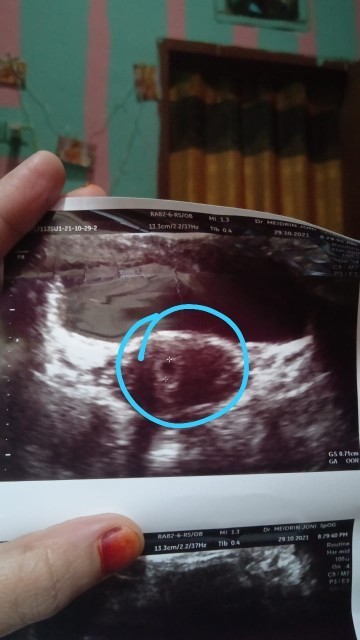

5 weeks

Bun ini aku usg pertama kli usia 5 minggu ini udh ada dedenya kan ya ? ?

5w belum ada dedeknya kak. pertama sy usg jg umur 5w2d masih kantung dan gs nya masih 1,sekian cm. nanti Insya Allah 1 bulan lg priksa lg udah bisa usg dr luar udah keliatan janin & djj nya juga sama gerakannya. sehat selalu ya, jgn cape-cape

saya dl usg 5 weeks br keliatan kantongnya aia bun, memang blm terlihat krn janinnya masih sangat kecil, sabar sambil terus berdoa dan makan makanan yg bernutrisi baik nanti usg lagi kl uda 8 weeks insyaallah ud keliatan bunsay